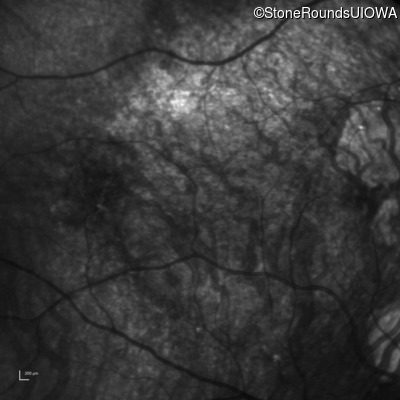

Infrared Fundus Photograph - Right - 20/20 -2 sc

Exemplar